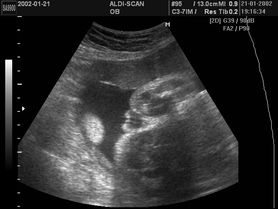

Płód w 10 tygodniu ciąży (zdjęcia)